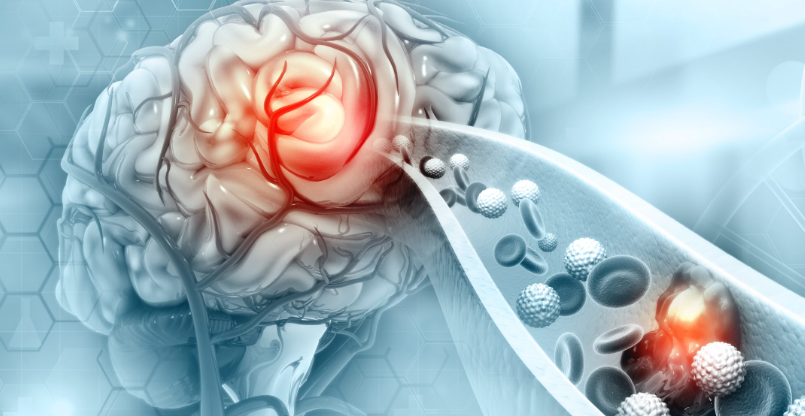

뇌졸중은 뇌의 일부로 혈액 공급이 중단되거나 감소하여 뇌 조직의 산소와 영양분을 감소시키거나 없앨 때 발생합니다. 몇 분 안에 뇌 세포가 죽기 시작하기 때문에, 뇌졸중 전조증상을 알고 있는 것은 대응하는데 큰 도움이 됩니다. 뇌졸중은 크게 혈관이 막혀 발생하는 허혈성 뇌졸중과 혈관이 터져 발생하는 출혈성 뇌졸중의 두 가지로 분류할 수 있습니다.